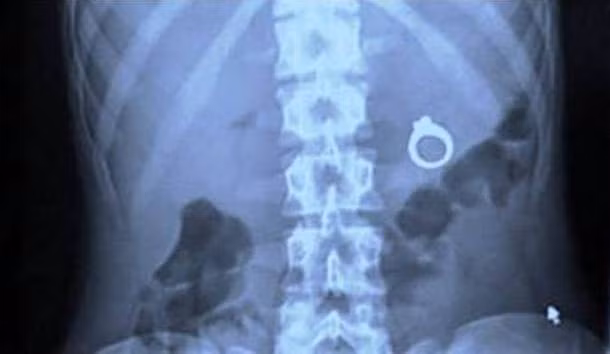

4. ...còn anh này thì không...

Đừng mất công tưởng tượng kỳ tích làm gì, anh chàng này thì chỉ đơn giản là đã chết cứng. Đây là phim chụp X-quang phục vụ công tác giám định tử thi, cho thấy anh này bị giết bằng một khẩu súng phóng đinh với hơn chục nhát bắn.